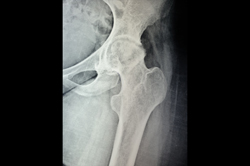

Neck Femur Fracture